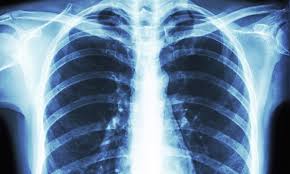

Medical x-ray is an imaging technique using x-rays to view the internal form of an object. To create the image, a beam of x-rays, a form of electromagnetic radiation, are produced by an x-ray generator and are projected toward the object. The x-rays that pass through the object are captured behind the object by a detector (either photographic film or a digital detector).

The purpose of this course is to convey a working knowledge of radiological physics anatomy and physiology and other related courses, and to provide a base of knowledge from which practicing medical x-ray students can make informed decisions about technical factors, diagnostic image quality, and radiation management for both patients and personnel.

Medical X-ray Technicians have a great responsibility in performing x-ray examinations in accordance with the established radiation standards for the safety of patient and medical personnel. Medical x-ray is a career choice with great, yet diverse, opportunities.